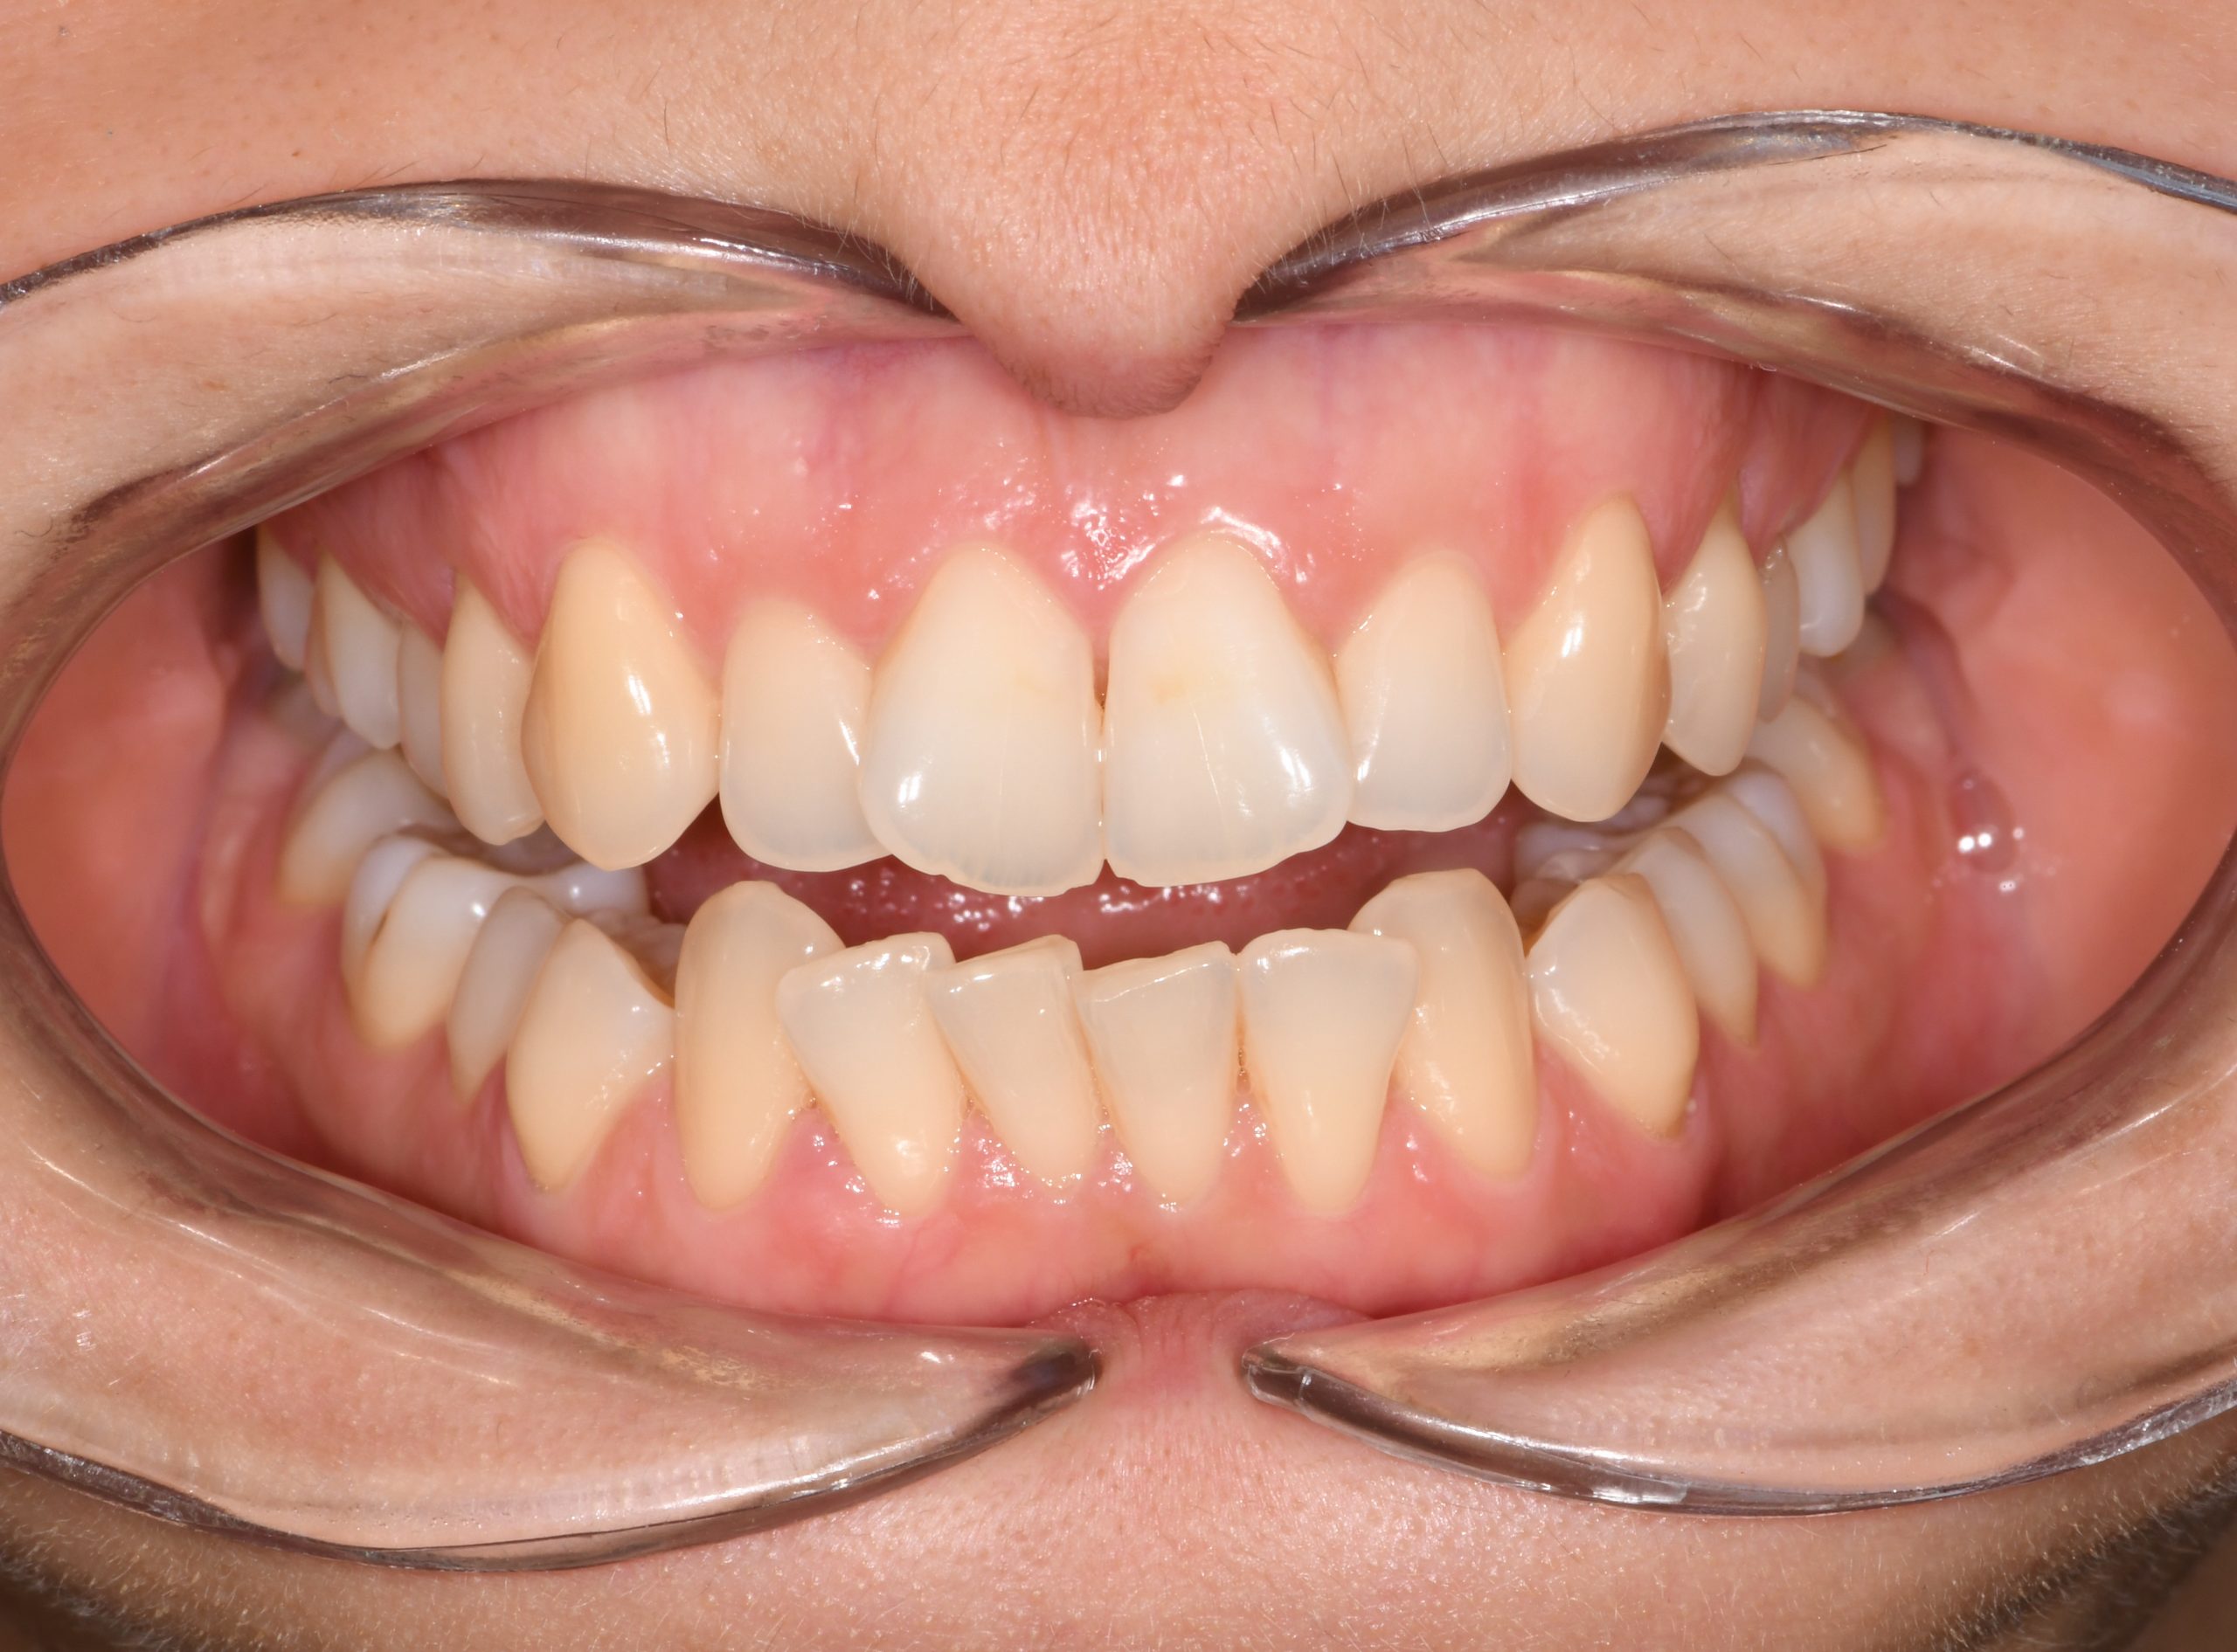

Az elmúlt évekből rengeteg szakmai referenciát tudnánk bemutatni, amelyek különböző fogszabályozási problémákat oldottak meg. Válogatva a több száz esetből, ezen az oldalon olyan képeket, információkat igyekeztünk bemutatni, amelyeknek a segítségével a jövőbeni pácienseinknek azt tudjuk üzenni: A Te fogsorod is lehet gyönyörű!